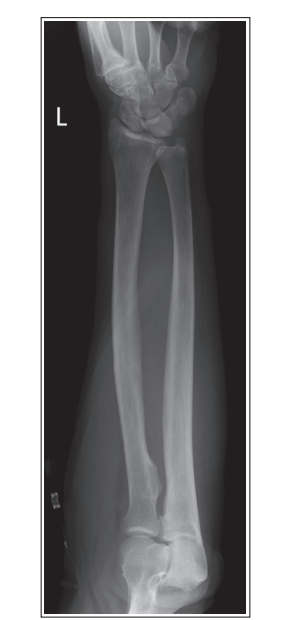

Proximal tib/fib are not superimposed

Elbow externally rotated and wrist internally rotated

Over superimposition of tib/fib

Elbow internally rotated